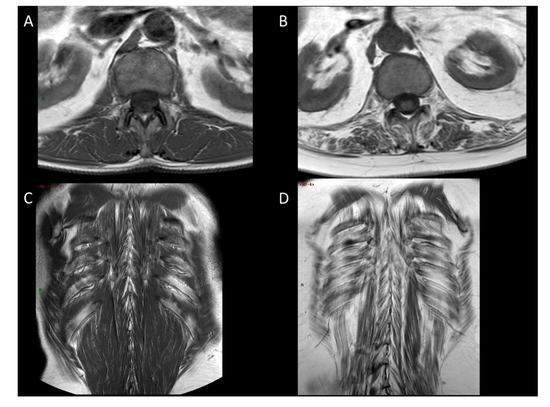

- Stage 0: normal appearance;

- Stage 1: early moth-eaten appearance, with scattered small areas of increased signal intensity on the T1 MR sequence;

- Stage 2a: late moth-eaten appearance, with numerous discrete areas of increased signal intensity (MRI) with beginning confluence, comprising less than 30% of the volume of the individual muscle;

- Stage 2b: late moth-eaten appearance, with numerous discrete areas of increased signal intensity (MRI) with beginning confluence, comprising 30–60% of the volume of the individual muscle;

- Stage 3: washed-out appearance, fuzzy appearance due to confluent areas of increased signal intensity (MRI), with muscle still present at the periphery;

- Stage 4: end-stage appearance, muscle replaced by increased signal intensity (MRI) connective tissue and fat, with only a rim of distinguishable fascia and neurovascular structures.